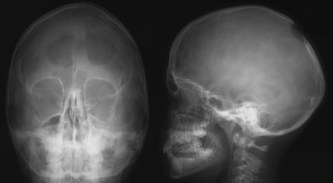

l’ostéopétrose

il s’agit également d’une maladie du remaniement de la structure osseuse, la voûte est très épaissie avec fermeture des sutures, qui peut rendre nécessaire une cranioplastie d’agrandissement crânien avec fraisage de la voûte cf. ci-dessous. à la différence de la dysplasie fibreuse, l’ostéopétrose entraîne une compression des canaux optiques qui peut nécessiter une décompression chirurgicale.